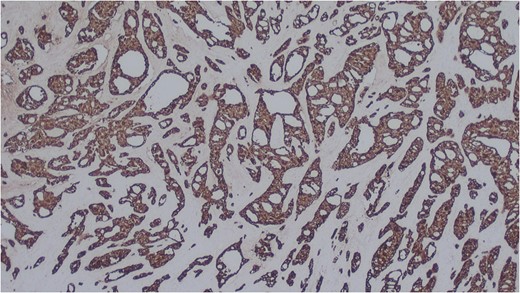

Histology of the mass confirmed sinonasal SDC. Tissue specimens showed cellular stroma extensively infiltrated by carcinoma composed of large eosinophilic cells with gland formation (Fig. 2). Widespread nuclear pleomorphism was evident. The sample was positive for cytokeratin-7 (CK7) (Fig. 3), epithelial membrane antigen (EMA), BerEP4 and demonstrated focal positivity for cytokeratin-5/6 (CK5/6). Post-operative MRI scans were requested to rule out residual disease or cervical lymphadenopathy (Fig. 4). Following review by Regional Head and Neck Cancer multi-disciplinary team and the oncologist, the patient was treated with a radical course of radiotherapy which was completed without complications. The patient has been reviewed regularly in the Head and Neck Cancer clinic with no evidence of recurrence at 18 months.

Salivary duct carcinoma cells highlighted by immunohistochemistry. CK7 (x25).